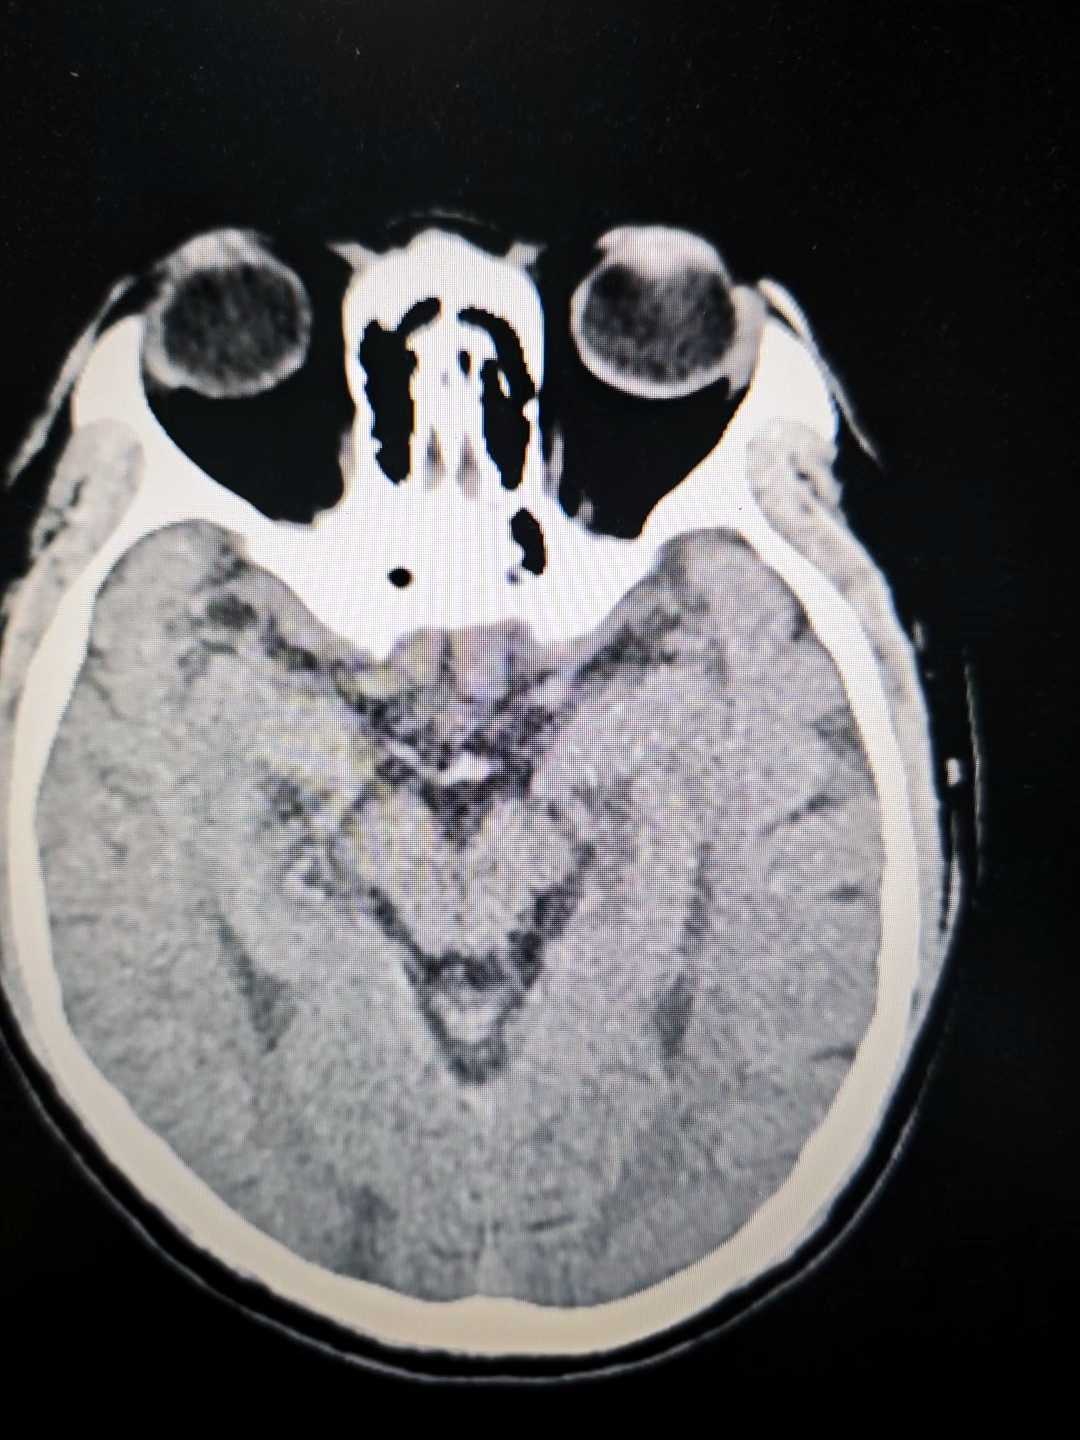

病例疑难:颅内多发病变

患者57岁,2天前因左上肢远端突发乏力体检发现颅内多发病变,目前患者无特殊不适。